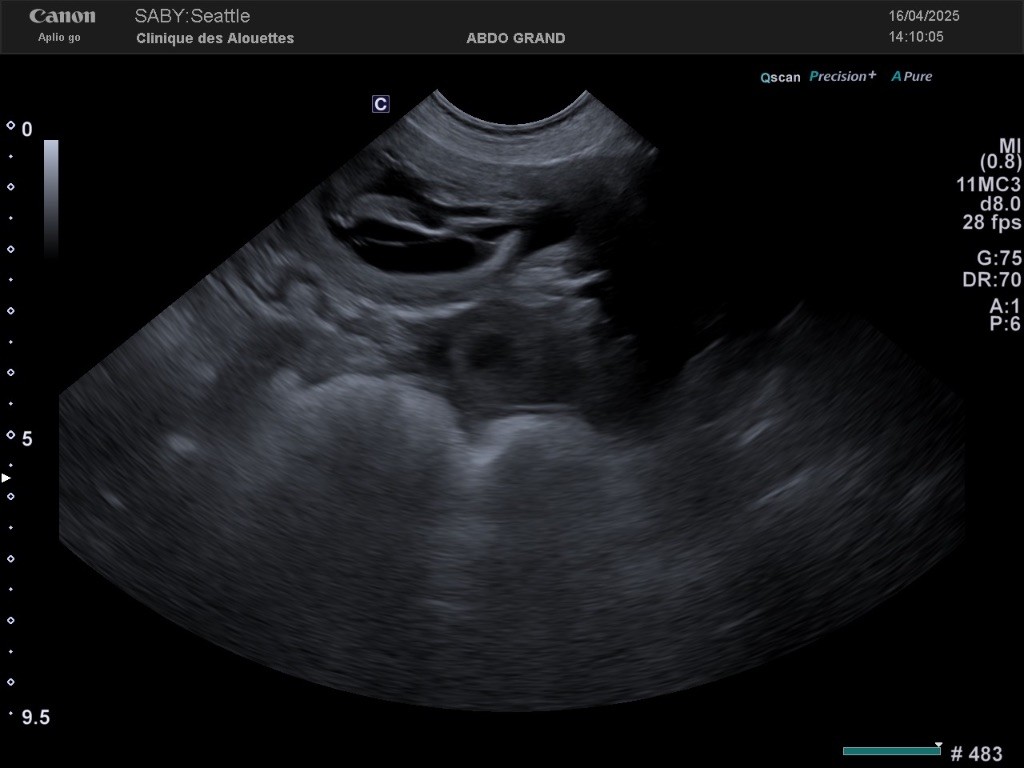

Seattle X Scrabble 2025

Affiche de saillie

Échographie comptage chiot